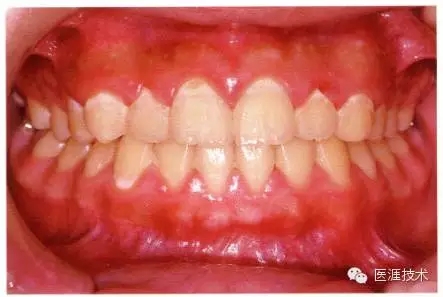

14歲男性牙齦炎的臨床圖像

14歲男性。刷牙狀態(tài)不佳。整顎浮腫性發(fā)紅、腫脹且刺激出血。牙頸部有早期齲(白斑)。